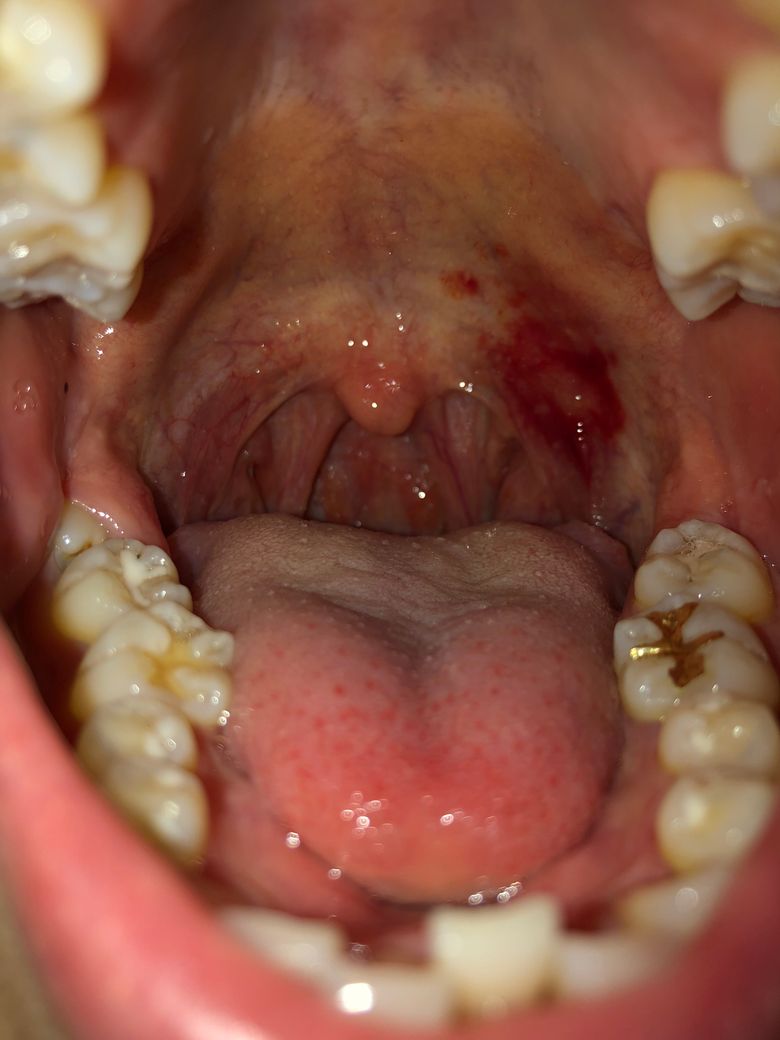

스케일링 석션에 피멍이 들었습니다

오늘 처음 스케일링을 받아봤는데

석션을 걸어두실때 입안이 자꾸 불편했는데 그냥 원래 그런가보다 하고 집에 와서 보니

그 자리에 이렇게 피멍이 들었네요… 이런 경우에는 어떻게 해야하나요?

• 1번 째 사진

석션이 목구멍쪽으로 가셔서 그런것같습니다. 자주 있는일은 아니지만, 가끔 발생할수 있습니다. 치과에 가셔서 말씀하셔도 되지만, 시간이 지나면 괜찮아 지는부분이라 크게 걱정은 안하셔도 될것같습니다.

일시적인 자극에 의해 생긴 것으로 보여지며 특별히 통증이 크지 않다면 시간이 지나면 회복됩니다. 큰 상처거나 외상이 아니며 이정도는 음식 섭취로도 나타날 수 있는 정도입니다. 일주일이내에 사라질 것으로 보이며 2주 이상 해당 병소가 나타나거나 더 커진다면 이때는 치과 방문 후 검사를 받아보시길 바랍니다.

치과치료시 석션을 필수적으로 해야하는데, 간혹 연조직에 상처가 나거나 발적이 되는경우도 있습니다.

연조직은 민감한 조직이라, 조금만 자극이 되도 그렇게 되곤 합니다. 물론 건들지 않는게 가장 좋겟지만, 그것이 쉽진 않기 때문입니다.